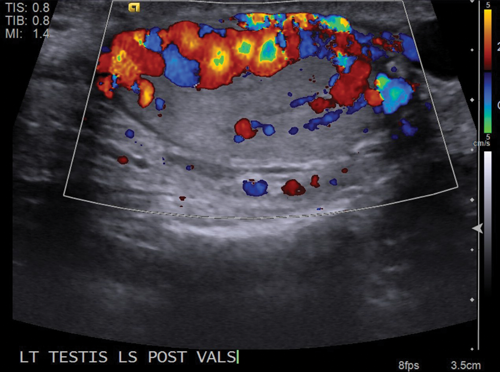

Figure 4: Colour Doppler confirms that the cystic appearing structures are dilated vessels.

Figure 5: Vessels demonstrate marked enlargement and reversal of

flow when the patient performs the Valsalva manoeuvre.

Dilated intratesticular veins are seen, which are usually adjacent to the mediastinum testis. On grey-scale ultrasound, this will appear as an anechoic tubular structure, which may have a similar appearance to an intratesticular cyst or tubular ectasia (Figure 3) and it is imperative to apply Doppler ultrasound in order to assess for vascularity (Figure 4). The flow within the varicocele will again be shown to increase and demonstrate reversal of flow when Valsalva manoeuvre is applied (Figure 5).